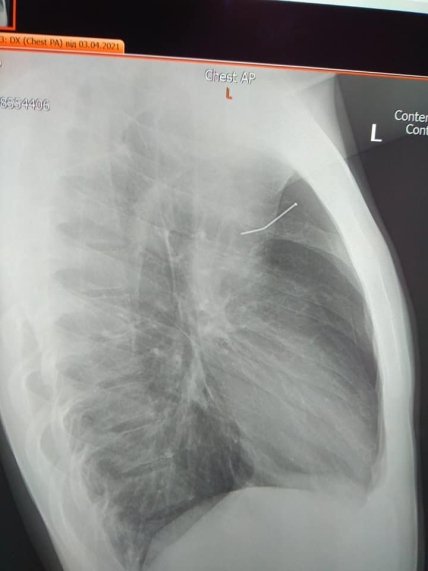

Как выяснилось, у парня была выраженная одышка, боль в левой половине грудной клетки. Также дежурный врач обнаружил, что легкое пробито гвоздем, развился левосторонний пневмоторакс - воздух попал в грудную клетку, сдавил левое легкое и смещал сердце вправо. На серии рентген-снимков врачи увидели строительный гвоздь в области левого легкого.

фото

"Ситуация была очень опасна - до аорты не доставало всего нескольких миллиметров. Если бы гвоздь пробил аорту, мы бы его уже не успели спасти, учитывая, что доехать из района во Львов так быстро невозможно. Но этому парню буквально повезло - гвоздь пробил легкое. Мы имели еще время на спасение ", - рассказал детский хирург Николай Мыкита.